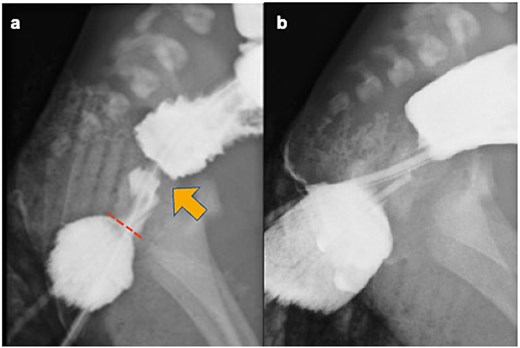

A 2-day-old male infant (birth weight 2618 g) was transferred to our department due to failure to pass meconium, vomiting, and abdominal distension. He was born spontaneously late pre-term after an uncomplicated delivery. Physical examination revealed abdominal distension and a normally positioned anus (Fig. 1). Abdominal X-ray revealed diffuse bowel distension, especially a dilated sigmoid colon (Fig. 2). We attempted suction of the meconium using a silicon catheter; however, the catheter could not be advanced >1 cm through the anal orifice. We subsequently tried to evaluate the rectoanal region using an anoscope and identified a rectal web with an orifice approximately 1 cm from the anal verge (Fig. 3a). We dilated the orifice using catheters measuring 4–10 Fr and placed the catheter beyond the orifice (Fig. 3b). Subsequently, meconium passage was confirmed. Abdominal ultrasonography confirmed the catheter positioned within the rectum (Fig. 4) and also revealed that no presacral mass existed. Lower gastrointestinal fluoroscopy showed the web located approximately 1 cm from the anal verge, with no fistula between the rectum and urethra (Fig. 5a). The images also showed contrast medium stopping above the pubococcygeal (PC) line (Fig. 5b). Following transanal decompression, definitive surgery was performed on Day 5 of life. Intraoperative findings showed that the stricture was located slightly more than 1 cm from the dentate line, and it consisted of a web with a hole (Fig. 6). RS was diagnosed based on these findings, and resection of the web and strictureplasty were performed. Although bougie dilation was required postoperatively, it was gradually tapered and discontinued by 1 year after surgery. No signs of restenosis were noted. Although bougie dilation was required postoperatively, the frequency of dilation decreased gradually and was no longer necessary 1 year after surgery.

Contrast enema. (a) Preoperative contrast enema showing the rectal web (arrow) located approximately 1 cm from the anal verge (dotted line), with no fistula between the rectum and urethra. (b) Preoperative contrast enema revealing contrast medium stopping above the PC line.